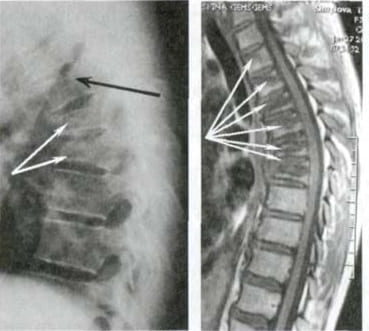

Погледнете този случай: това е гръбначният стълб на 44-годишен човек, който показва дегенеративни промени, характерни за напреднала възраст. Преди подобно разрушение се случваше след 60, а днес – още на 40. Тези промени напредват с възрастта и ако бъдат пренебрегнати, това означава риск от пълна загуба на подвижност!

Но болката в гърба е особено опасна – поради специфичната структура на хрущяла и междупрешленните дискове, разпадането в областта на гръбначния стълб настъпва 3–4 пъти по-бързо, отколкото в другите стави!

Погледнете тези снимки – това е съдбата на тези, които не са реагирали навреме. Днес те са безпомощни и много от тях нямат никого, който да им помогне. Наистина ли искате такъв край?

- Всички тези снимки показват, че гелът „Reumax” възстановява здравето на ставите, дори в случаи, когато диагнозата изглеждаше като смълртна присъда. Без хирургични интервенции, без мъчителни болки, всички пациенти успяха да постигнат стабилно подобрение и да се върнат към нормалния си живот. ТОЗИ ГЕЛ НАПЪЛНО ПРОМЕНИ ХОДА НА ЛЕЧЕНИЕТО НА СТАВИТЕ И ГРЪБНАКА!